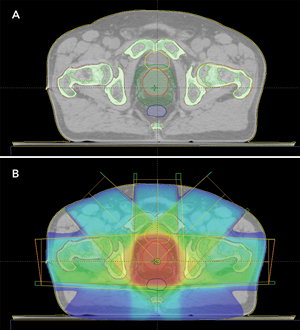

Standard treatment planning for EBRT

In EBRT for prostate cancer, high-energy x-ray beams from multiple directions deposit energy (dose) within the tumour (prostate) to destroy cancer cells. The standard process for EBRT treatment planning is shown in Box 1(A). The first step is patient imaging (a CT scan sometimes combined with MRI). The treatment targets (the prostate and sometimes the seminal vesicles) and important normal tissues (the rectum, bladder, and femoral heads) are then manually defined from the scans (Box 2). Modern radiotherapy machines offer improved treatment accuracy through better visualisation and the correction of errors in patient setup, making target delineation the most significant uncertainty in radiotherapy planning.

In standard treatment planning, if MRI is used for visualising the prostate, then the scans from MRI and CT are aligned to transfer the structure contours defined by MRI to the CT scans for accurate dose calculation. The defined prostate volume is then expanded to become the larger, planning target volume for treatment. This allows for uncertainties in delineation and patient setup, and for prostate movement. The next step is the use of computer planning tools to determine the directions, strengths and shapes of the treatment beams used to deliver the prescribed dose to the defined target, while minimising the dose to normal tissues. Finally, the patient is carefully positioned and the treatment is delivered. The optimal way to align the patient for treatment is to use small implanted fiducial markers in the prostate. These are visible under x-ray imaging and show the precise position of the prostate within the body. Image guidance is used to align the treatment target each day for the entire radiotherapy course.